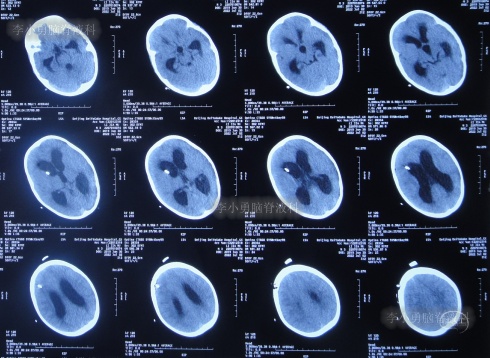

第3家医院治疗16天即2022年6月9日,不但依然发热,而且查头颅CT示脑室稍扩张(图-3)。

图-3:2022年6月9日头颅核磁

但该院治疗12天即2022年6月29日,复查头颅核磁脑室扩张进一步加重(图-6)。

图-6:2022年6月29日头颅核磁

入院当天查头颅CT示脑室扩张(图-8)。

图-8:2022年7月1日入院时头颅CT